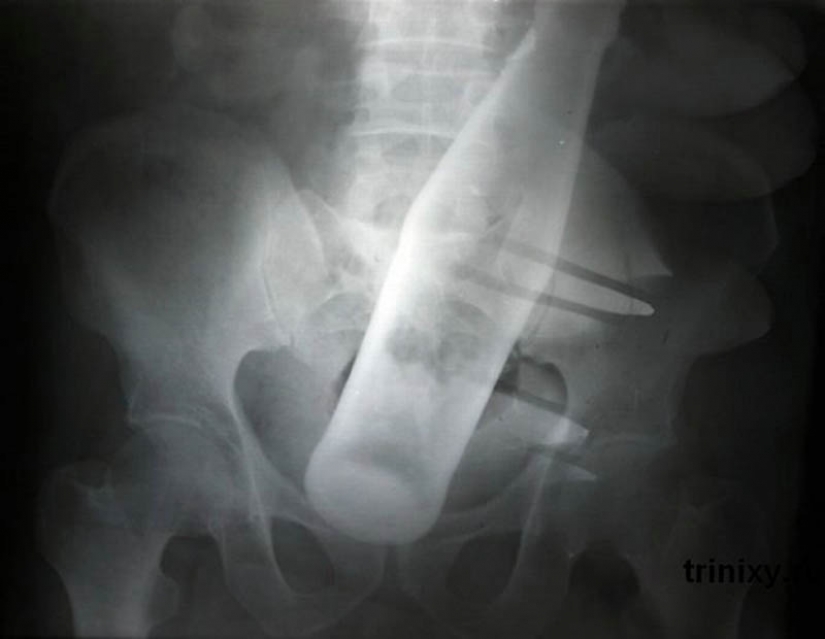

20. Botella de "Pepsi" en el ano de 60 años de edad, hombre.